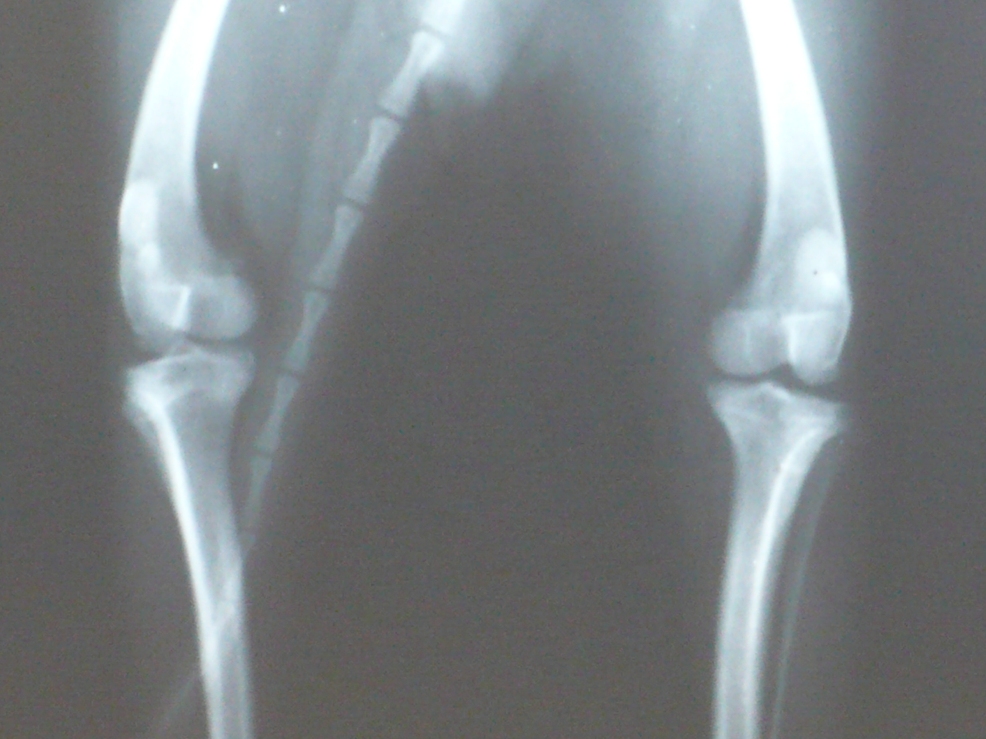

Вот снимок с разным увеличением суставов Микуши. yamagutti, обратите, пожалуйста, внимание и на скакательные суставы, хоть их и мало видно

• 1_1.JPG

Чихуахуа (1.JPG)

169,1 KB · Просмотры: 201

• 1_2.JPG

Чихуахуа (2.JPG)

238,2 KB · Просмотры: 206

• 1_3.JPG

Чихуахуа (3.JPG)

246,3 KB · Просмотры: 208

• 1_4.JPG

Чихуахуа (4.JPG)

299,4 KB · Просмотры: 214